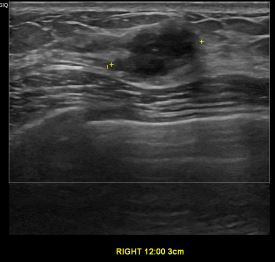

상기환자는 외부건강검진이상소견 정밀검사위해 내원하신  40대 중반

여성분으로 의심스러운 우측유방혹 조직검사 시행해 유방암으로 진단되었습니다